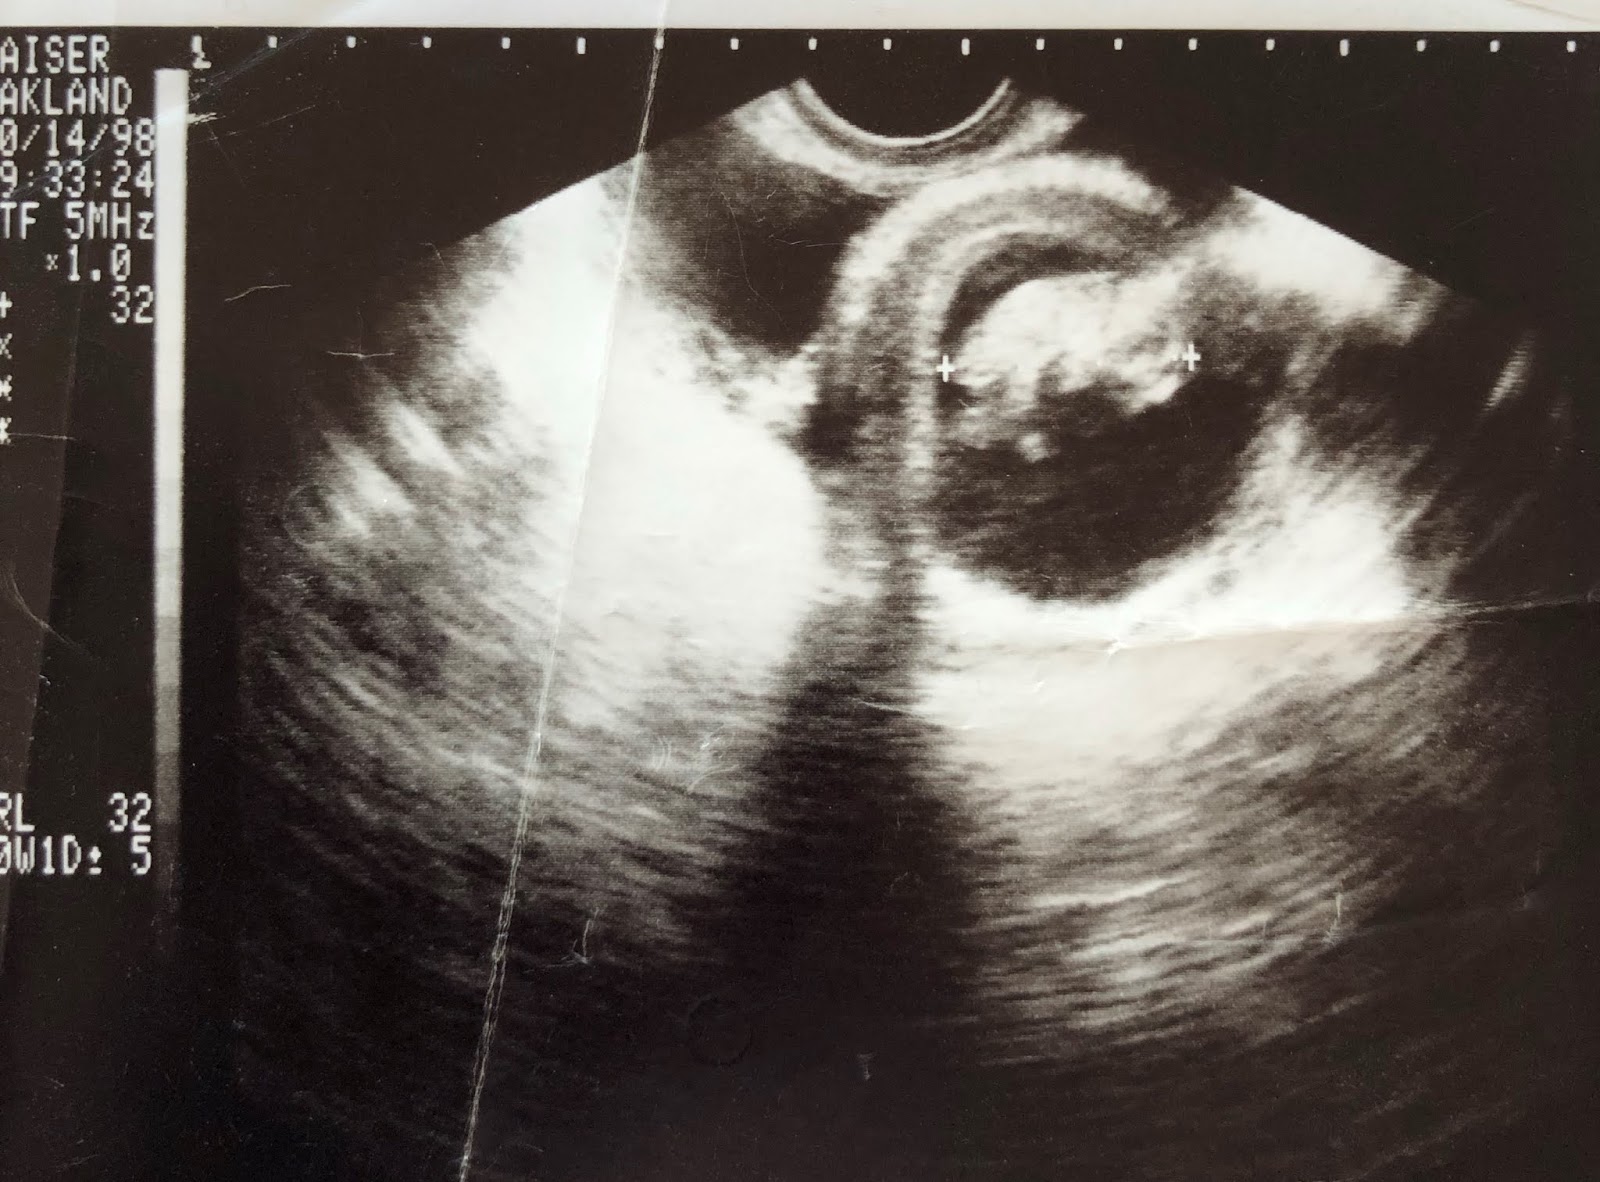

Baby Chris is Ten Weeks Old

Baby Chris has put on some serious weight this week: a whopping 77% increase, according to the Endowment for Human Development. He or she now weighs about half an ounce and is the size of a lime.

P.S.—The ultrasound photo at the top of this post was donated by Secular Pro-Life supporter Jean I., and it depicts her son in 1998. She also sent in her son’s senior class photo, 17 years later!